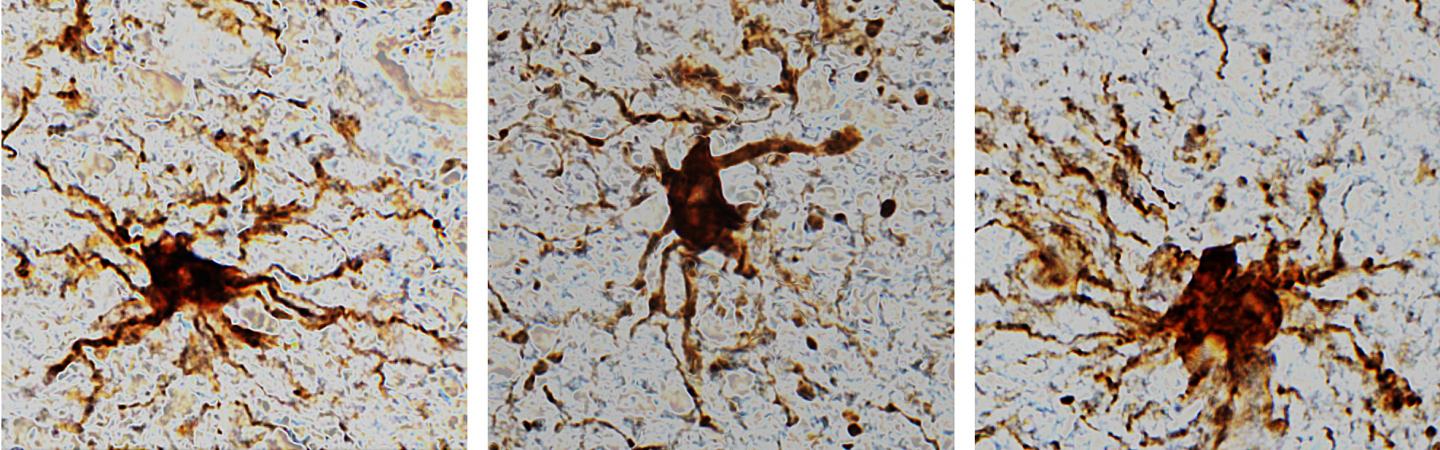

image: 'Zombie' cells come to life after the death of the human brain.

These 'zombie genes' -- those that increased expression after the post-mortem interval -- were specific to one type of cell: inflammatory cells called glial cells. The researchers observed that glial cells grow and sprout long arm-like appendages for many hours after death.

"That glial cells enlarge after death isn't too surprising given that they are inflammatory and their job is to clean things up after brain injuries like oxygen deprivation or stroke," said Dr. Jeffrey Loeb, the John S. Garvin Professor and head of neurology and rehabilitation at the UIC College of Medicine and corresponding author on the paper.

A third group of genes -- the 'zombie genes' -- increased their activity at the same time the neuronal genes were ramping down. The pattern of post-mortem changes peaked at about 12 hours.